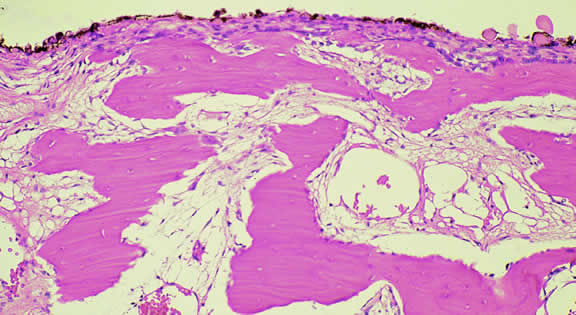

Macroscopically, the appearance of eyes with uveal metastases is somewhat variable. In most instances the uveal tract is diffusely thickened by an infiltrate of white, pink, or yellow tissue (Fig. 50). Metastases occasionally have a multinodular growth pattern, and a few larger lesions are oval in configuration (Fig. 51). Bruch's membrane almost always remains intact, however. Although there are exceedingly rare exceptions to the rule, one generally can conclude that a mushroom-shaped tumor of the choroid is a malignant melanoma.

Microscopically, the uveal stroma is infiltrated by nest, cords, islands, and sheets of tumor cells whose general appearance and arrangement is dependent on the identity of the primary neoplasm. Most of the breast and lung tumors that metastasize to the eye are mucous-secreting adenocarcinomas. In such cases special stains such as Alcian blue, PAS, or mucicarmine are used to demonstrate the presence of intracytoplasmic mucin (Fig. 52). In most instances the pathologist can readily distinguish between a primary uveal melanoma and metastatic carcinoma in routine sections. Immunohistochemistry may be helpful in exceptional cases. Carcinomas are distinguished by positive immunoreactivity for epithelial markers such as cytokeratins and epithelial membrane antigen. Most melanomas stain with S-100 protein and vimentin and a variety of other markers including so-called melanoma specific antigen HMB-45, melan A, and microphthalmia factor. Occasionally, immunohistochemistry can confirm or provide clues to the identity of the primary tumor by demonstrating the presence of tumor specific antigens such as prostate specific antigen (PSA) in prostatic carcinoma or thyroglobulin in thyroid. Distinguishing between a primary uveal melanoma and choroidal metastasis from skin melanoma or another primary nonocular pigmented neoplasm may be challenging.197,198